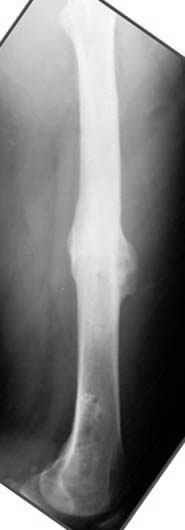

Несколько снимков из моей коллекции, чтобы разьяснить, почему мы до сих пор делаем различные варианты остеотомии.

На рисунке N1 предоперационный план лечения ложного сустава шейки бедра- линия ложного сустава, угол и направление введения импланта, клиновидная остеотомия в градусах и миллиметрах, второй снимок после коррекции, расчет, на сколько удлиняется конечность и размеры импланта;

N3 рисунок окончательный снимок, после операции моя рентгенограмма должен выглядеть примерно как эта картина. На N4 снимке клин перед удалением; N5 послеоперации 3 нед.; N6 окончательная рентгенограмма.